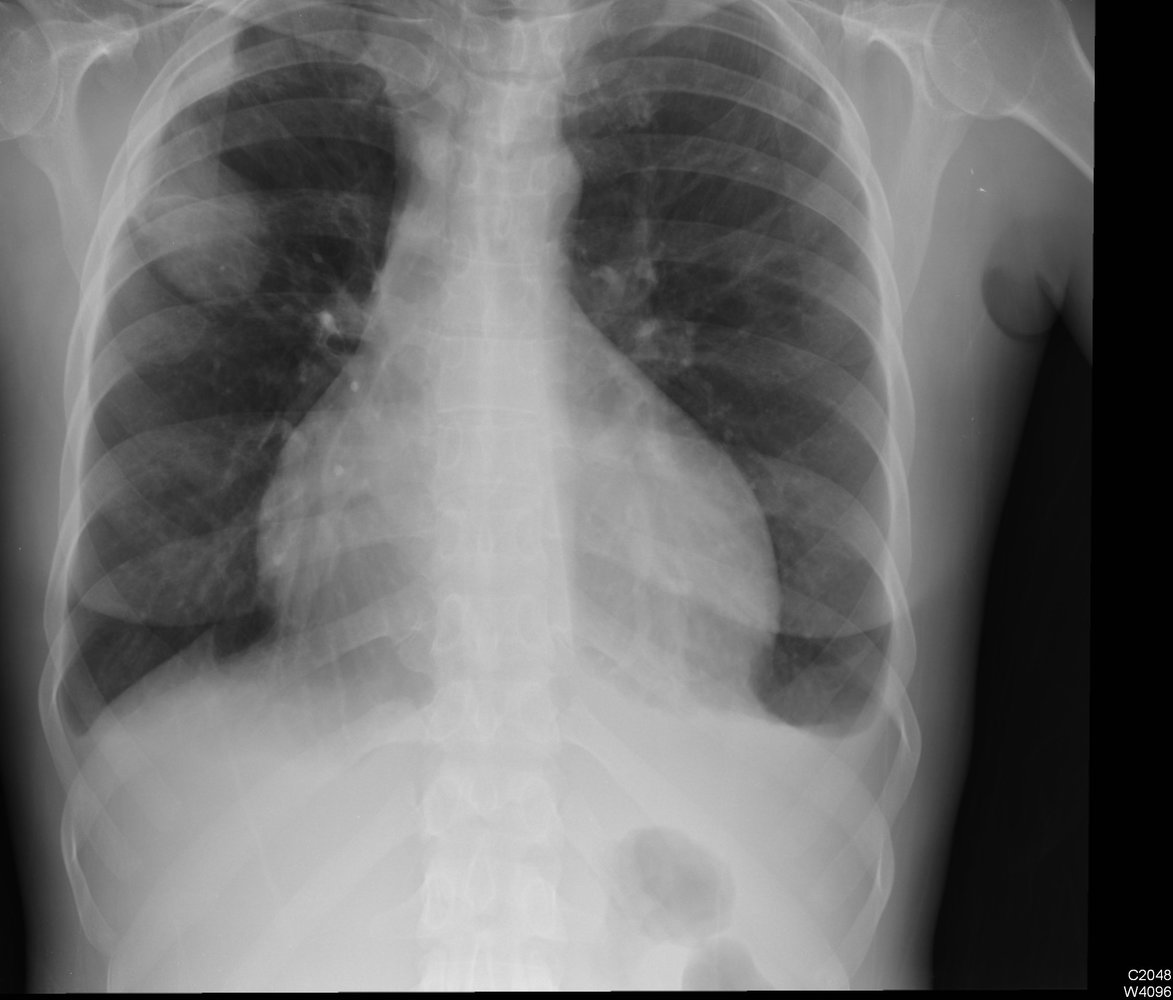

Imaging [2][3]

• Obtain HRCT chest in all patients with suspected ABPA.

• Typical findings include:

• Central bronchiectasis

• Pulmonary infiltrates

• Mucoid impaction

• Mosaic attenuation

• Tree-in-bud sign

• Fibrosis

• Centrilobular nodules